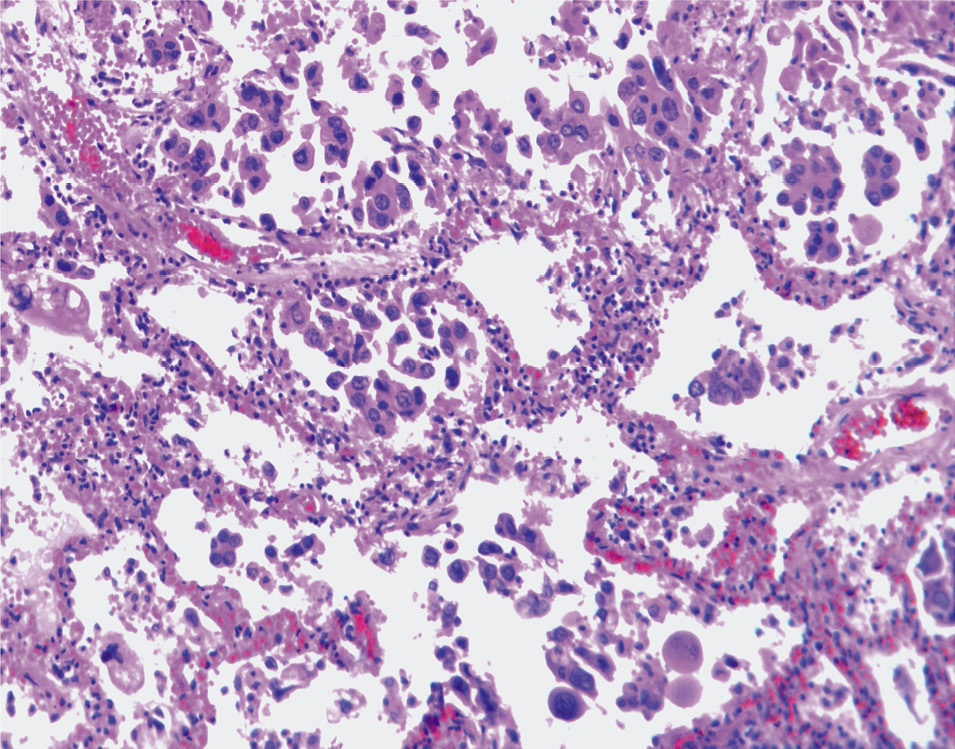

Определяются морфологические признаки метастазирования аденокарциномы во внутренние органы: в печени выявляются серой окраски узлы, расположенные друг от друга на расстоянии 7–8 см, в диаметре от 0,7 до 1,5 см; в селезенке определяется несколько узлов, имеющих серую окраску, в диаметре от 0,5 до 0,7 см; в хвосте поджелудочной железы имеется участок серого цвета с нарушением дольчатости, размерами 1,5×2,0 см, без четких границ с признаками прорастания в парапанкреатическую клетчатку. Лимфатические узлы без изменений. При гистологическом исследовании определяются опухолевые клетки округло-овальной формы средних или крупных размеров с гиперхромными округлыми или овальными ядрами, заполняющими всю клетку или смещенными к одному из ее полюсов, и преимущественно гомогенной цитоплазмой, образующие железистые структуры (рис. 4, 5).

Рис. 4. Среди атрофированных печеночных балок определяются комплексы опухолевых клеток с формированием железистых структур и участками кровоизлияний. Окраска гематоксилином и эозином, ×900.

Рис. 5. Микроскопическая картина опухолевой ткани, представленной полиморфными клетками, с патологическими митозами и участками фиброзирования в строме опухоли. Опухолевые клетки врастают в поджелудочную железу, с образованием железистых структур. Окраска гематоксилином и эозином, ×400.